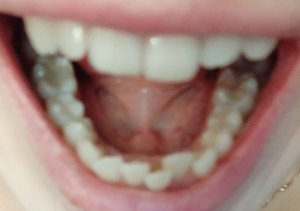

Для установления брекетов врач мне рекомендует удалить верхнюю справа четверку, чтобы поставить на ее место клык, и нижний второй резец справа, аргументируя тем, что так будет быстрее идти лечение, по словам врача корень у этого резца оголен и подвижен (хотя я не чувствую, чтобы он шевелился) и, что все равно в дальнейшем этот зуб я потеряю (и никто, кроме стоматологов не будет замечать, что резцов нижних у меня 3, вместо 4х).

Правда ли то, что этот зуб (резец второй) не здоров? И лучше удалить его, а не 4 нижнюю справа?